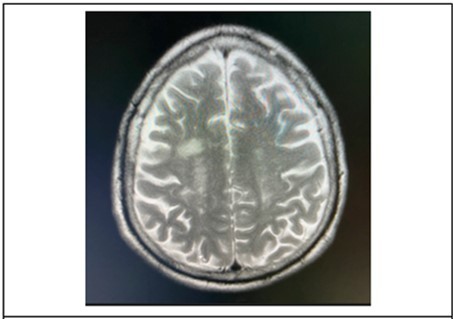

Cranial MRI plain and with contrast was requested by the ophthalmology service to further investigate on the brainstem. The subsequent study done 21 days after onset of symptoms, revealed patchy bright flair signals were noted in the subcortical white matter and periventricular area. (Figure 6) The orbits, midbrain, pons were regarded as unremarkable.

Figure 6.It showing T2 weighted, axial MRI scans at the level of the lateral ventricles, revealed patchy bright flair signals were noted in the subcortical white matter and periventricular area.